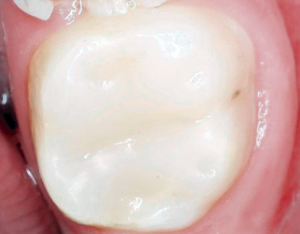

El plan de tratamiento consistió en llevar a cabo una pulpotomía en el órgano dental 46 con Biodentine, proteger el Biodentine con ionómero de vidrio modificado con resina Fuji II LC®, rehabilitación con Solare X A2 (GC America). (Figuras 3 a 8).

Lo anteriormente expuesto concuerda con el caso del paciente aquí presentado, cuyos resultados radiográficos en tres periodos: posoperatorio, un mes y un año de tratamiento, evidencian una respuesta favorable al seguimiento clínico (figuras 9 y 10).